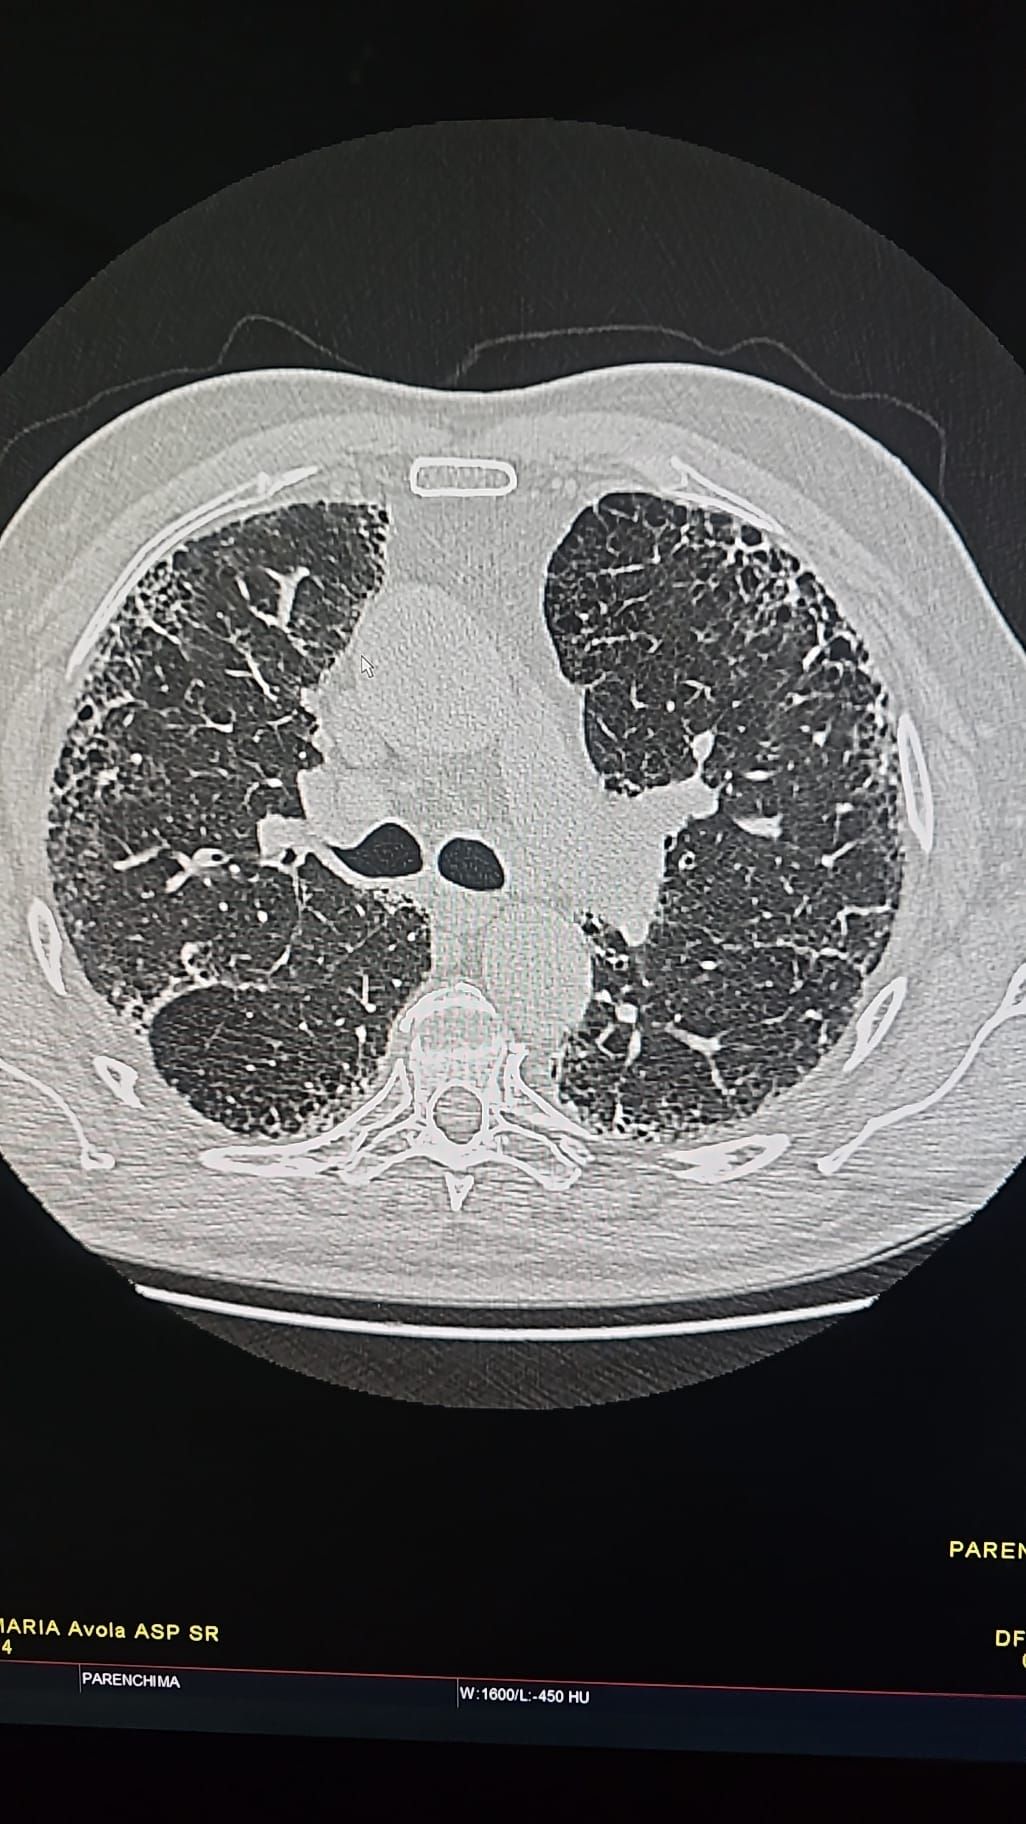

La mia formazione medica è avvenuta presso l'Università degli studi di Catania, ove ho conseguito la laurea magistrale, discutendo una tesi improntata sullo studio delle patologie oncologiche polmonari, ottenendo la votazione massima, e lode. Successivamente ho conseguito la laurea specialistica presso la stessa Università, discutendo una tesi sulla patologie polmonari da infezione da Covid 19, conseguendo il titolo di medico chirurgo specialista in Radiodiagnostica, con la votazione massima, e lode.

Foto e video

• TAC Total body

250 €